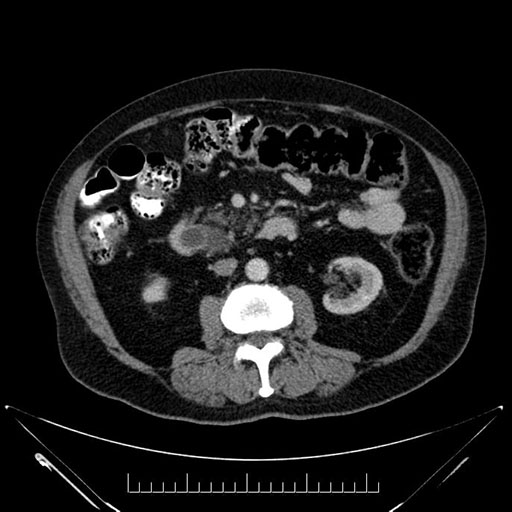

Axial - stented